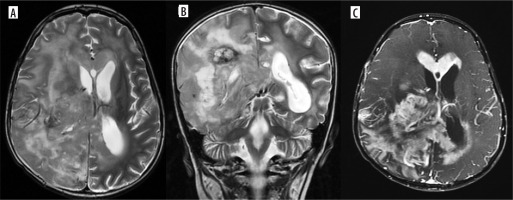

Figure 4

Multifocal glioblastoma. Axial and coronal T2 images (A, B), shows a diffusely infiltrative T2 heterogenous tumour, with heterogenous enhancement (C) in the right parieto-temporal lobe and the thalamus showing necrosis, haemorrhage and extensive surrounding non enhancing oedema. There is subependymal involvement and mild hydrocephalus, likely due to partial obstruction of the right foramen of Monro. Another discrete lesion is seen in the corpus callosum anteriorly